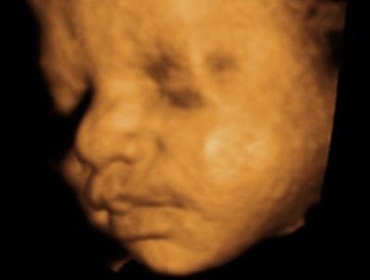

Saptamana 30 de sarcina

Principala evolutia a copilului fata de saptamana trecute este acumularea rapida de grasime.